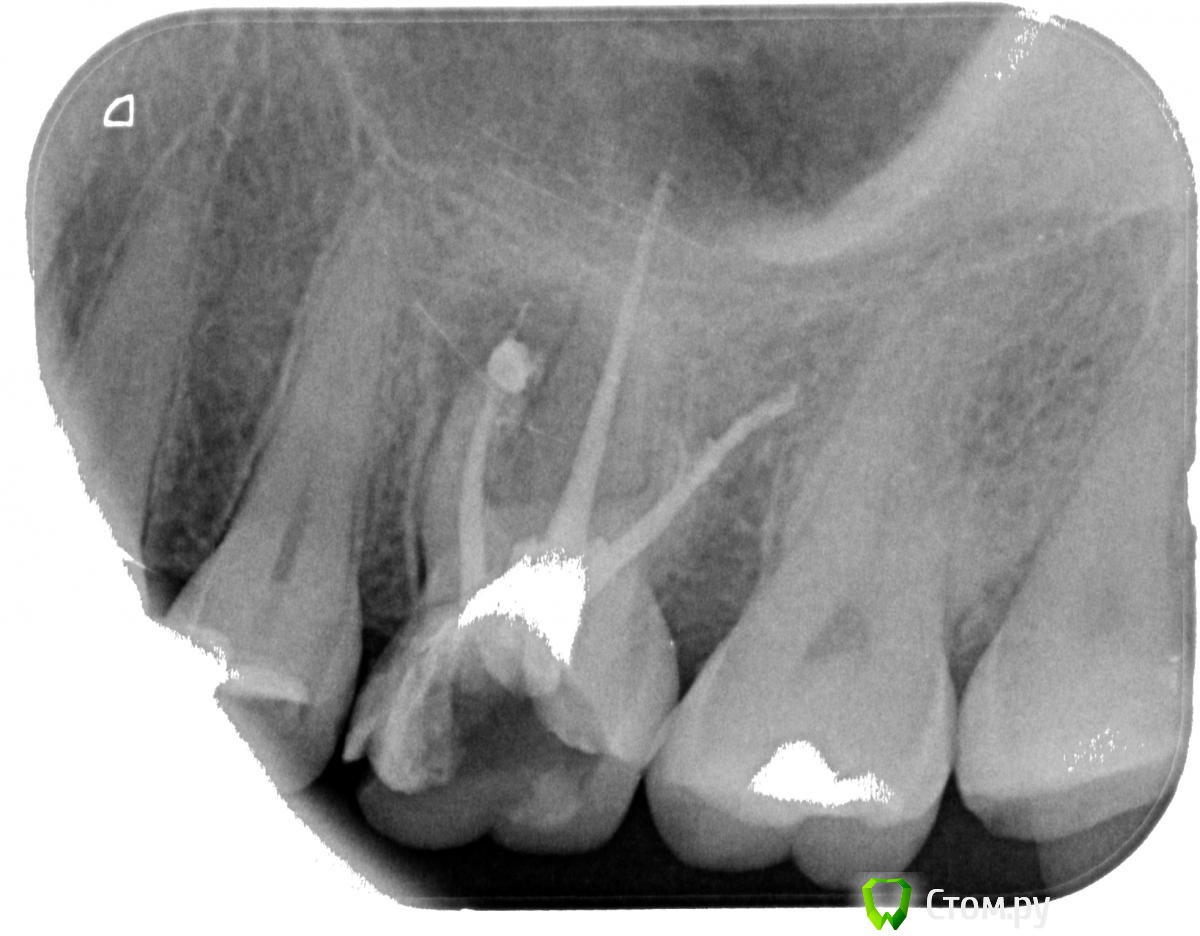

oksanab Опубликовано 9 октября, 2014 Поделиться Опубликовано 9 октября, 2014 (изменено) мне лечили 26-й зуб и медсестра озвучила, что нет 40-го и 38-го штифта .В итоге врач поставил просто эндометазон без гуттаперчей. Это я узнала, когда мне зуб вскрыли и стали перепломбировывать один канал, ввиду того, что паста там была не застывшая, мягкая. Является ли это ошибкой терапевта, когда паста мягкая в канале? . Плохо ли, когда эндометазон без гуттаперчи(судя по всему не было 40-го )? И почему ,как вы думаете, уже другой терапевт перелечила только центральный канал и не тронула остальные, хотя я просила об этом(потому что ортопед попросил). Она только загерметизировала остальные два канала(возможно апексом, не знаю, а вот центральный канал апексом верхушку корня залила). Достаточно ли этого, или лучше все-таки перепломбировать и два остальных канала?(в одном из них судя по всему перфорация, на другом - лекарство выведено за канал ,а может эндометазон за канал с лечебной целью выведен.... В выписке предыдущий врач не отметил, какое конкретно лекарство за каналом было выведено. Прилагаю снимки, на первом три канала 12 лет назад, на втором и третьем - перелечивание и пломбировка эндометазоном всех трех каналов(просто два снимка в разных клиниках ,но суть одна), да еще и скол зуба появился небольшой(ортопеды говорят, поправимо), и на третьем снимке перепломбировали только центральный канал. Нормально ли перепломбировали хоть средний канал? на мой взгляд как-то верхушка его странно расширилась, была поуже на 2-м и 3-м снимке(пломбировали методом латеральной конденсации). Подскажите пожалуйста, что думаете? Изменено 9 октября, 2014 пользователем oksanab Ссылка на комментарий

Cleric Опубликовано 9 октября, 2014 Поделиться Опубликовано 9 октября, 2014 (изменено) В вашем зубе "пропущен" ещё один канал в переднем щечном корне. Зуб на адекватное перелечивание. В этом зубе минимум 4 канала. Изменено 9 октября, 2014 пользователем Cleric Ссылка на комментарий

Паращук Роман Опубликовано 10 октября, 2014 Поделиться Опубликовано 10 октября, 2014 (изменено) Сравните снимки.Ты видишь суслика? Нет? И я нет,а он есть! (с)ПиСи Пропущенный канал,перфорация,мат-ял за верхушкой. Зуб уже визу в плевательницу открыл.http://s020.radikal.ru/i708/1410/b7/ad9c402a2f4c.jpghttp://s43.radikal.ru/i099/1410/5f/23581663b182.jpg Изменено 10 октября, 2014 пользователем Паращук Роман Ссылка на комментарий